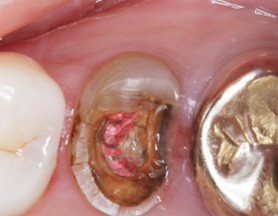

치근단 염증

캐스팅 포스트 제작

캐스팅 포스트

크라운치료

크라운을 하기 전에 신경 치료를 위해 뚫어 놓은 구멍을 단단한 재료로 메우는 것이 필요합니다. 보통 코어, 핀 포스트, 캐스팅포스트,

파이버 포스트와 같은 종류가 있으며 외부에서 힘을 가해져도 치아가 부러지지 않고 남은 치아의 구조물에 잘 붙어 있도록 합니다.

충치가 많이 진행되어 치아 부분이 많이 없거나 치아가 약한 경우에 필요합니다.